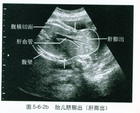

可明確骨缺損的大小,膨出的內容物及其來源,及其他合併的畸形。

(3)膨出之包塊透光試驗陽性,顱骨X線片能明確顱骨裂的部位和大小。少數腦膜腦膨出者可行CT掃描,了解腦組織膨出情況。